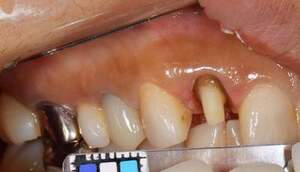

治療前で残存歯質がほとんどみられません。

残存歯質はないが、歯根は長いことを確認。

MTM中。頬側には審美面の回復のために仮歯がついています。

歯からはフック、隣り合った歯にはワイヤーが渡してあります。そこにゴムをひっかけて歯を挺出します。